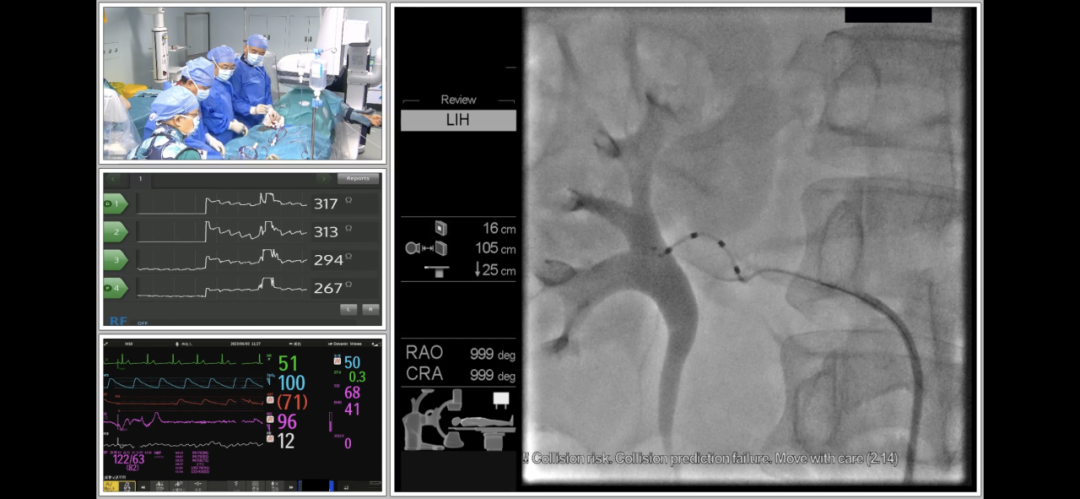

马翔教授和谢翔教授在海南博鳌研究型医院顺利完成RDN手术

术中经股动脉入路,首先对腹主动脉行非选择性造影,以确认肾动脉及副肾动脉开口位置。后通过Launcher导引导管分别对左右肾动脉行选择性造影,在确认血管直径和位置后,决定对分支和主支均进行射频消融治疗。采用由远及近,先分支后主干的消融策略,先后消融了左侧和右侧肾动脉远端分支血管和主干血管,共进行了59个位点的消融,术后造影显示肾动脉血流正常,无痉挛,无狭窄,无明显血管损伤,手术获得圆满成功。